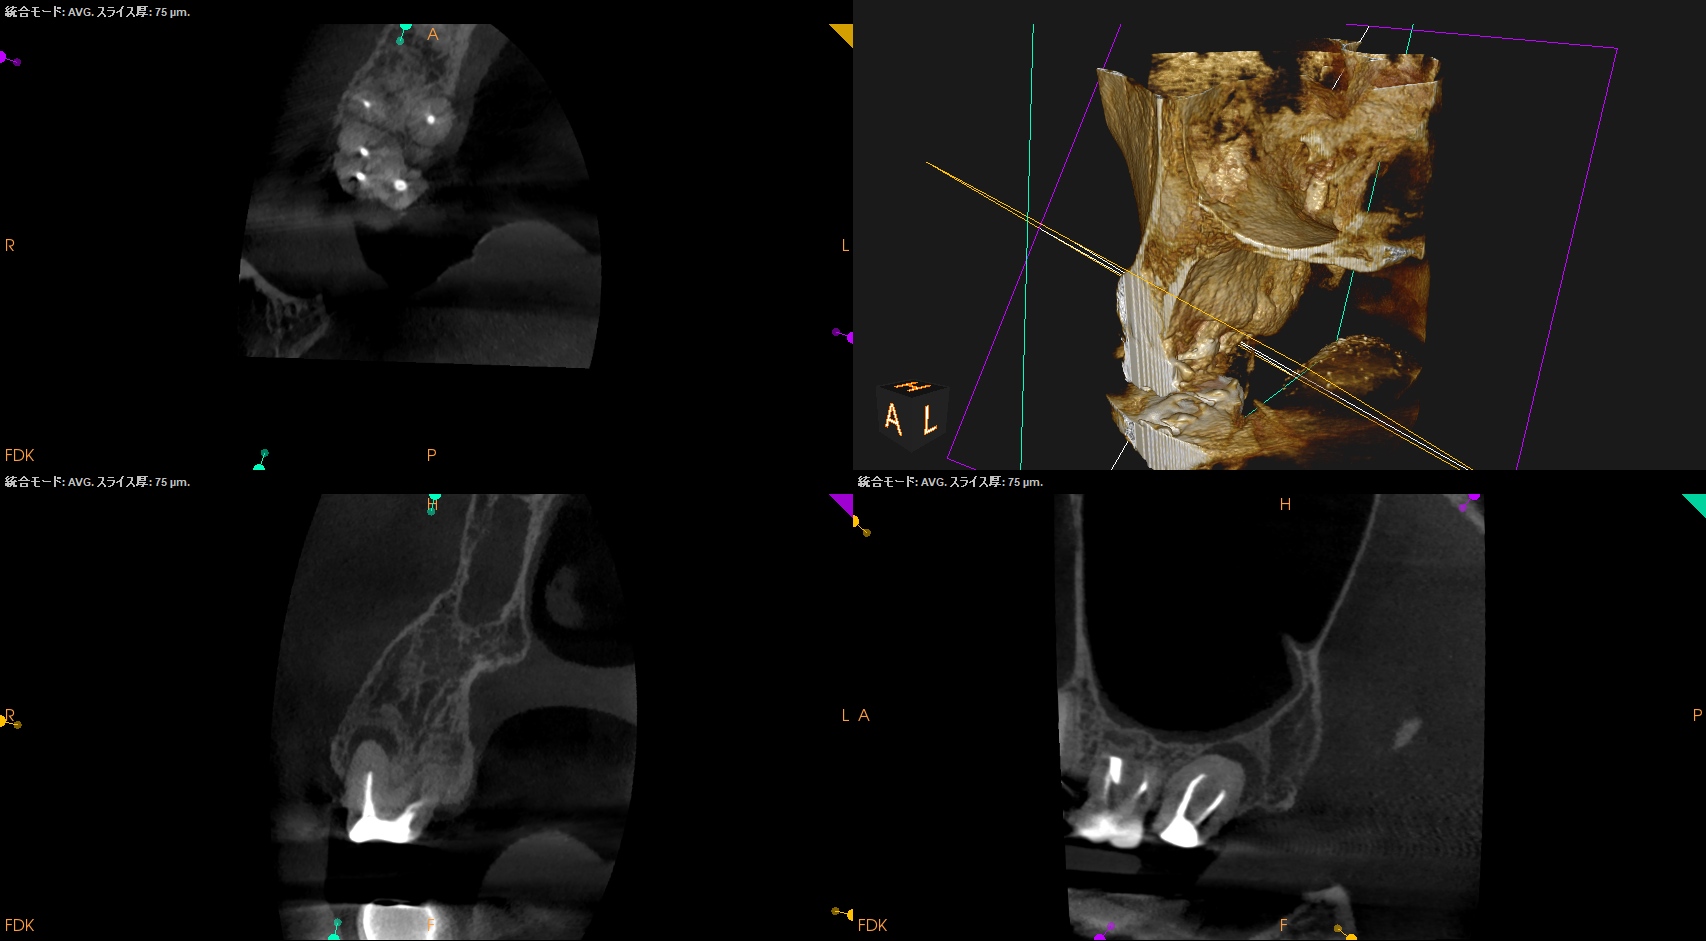

術後に口腔内PA, CBCTも撮影した。

MB

DB

P

ということで問題が客観的にないことがわかる。